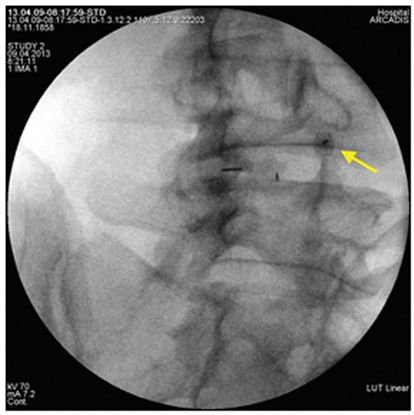

Figure 2. Lateral intraoperative radiograph of the lumbar spine. The tip of the puncture needle is located in the upper outer quadrant of the intervertebral foramen LIV-V |